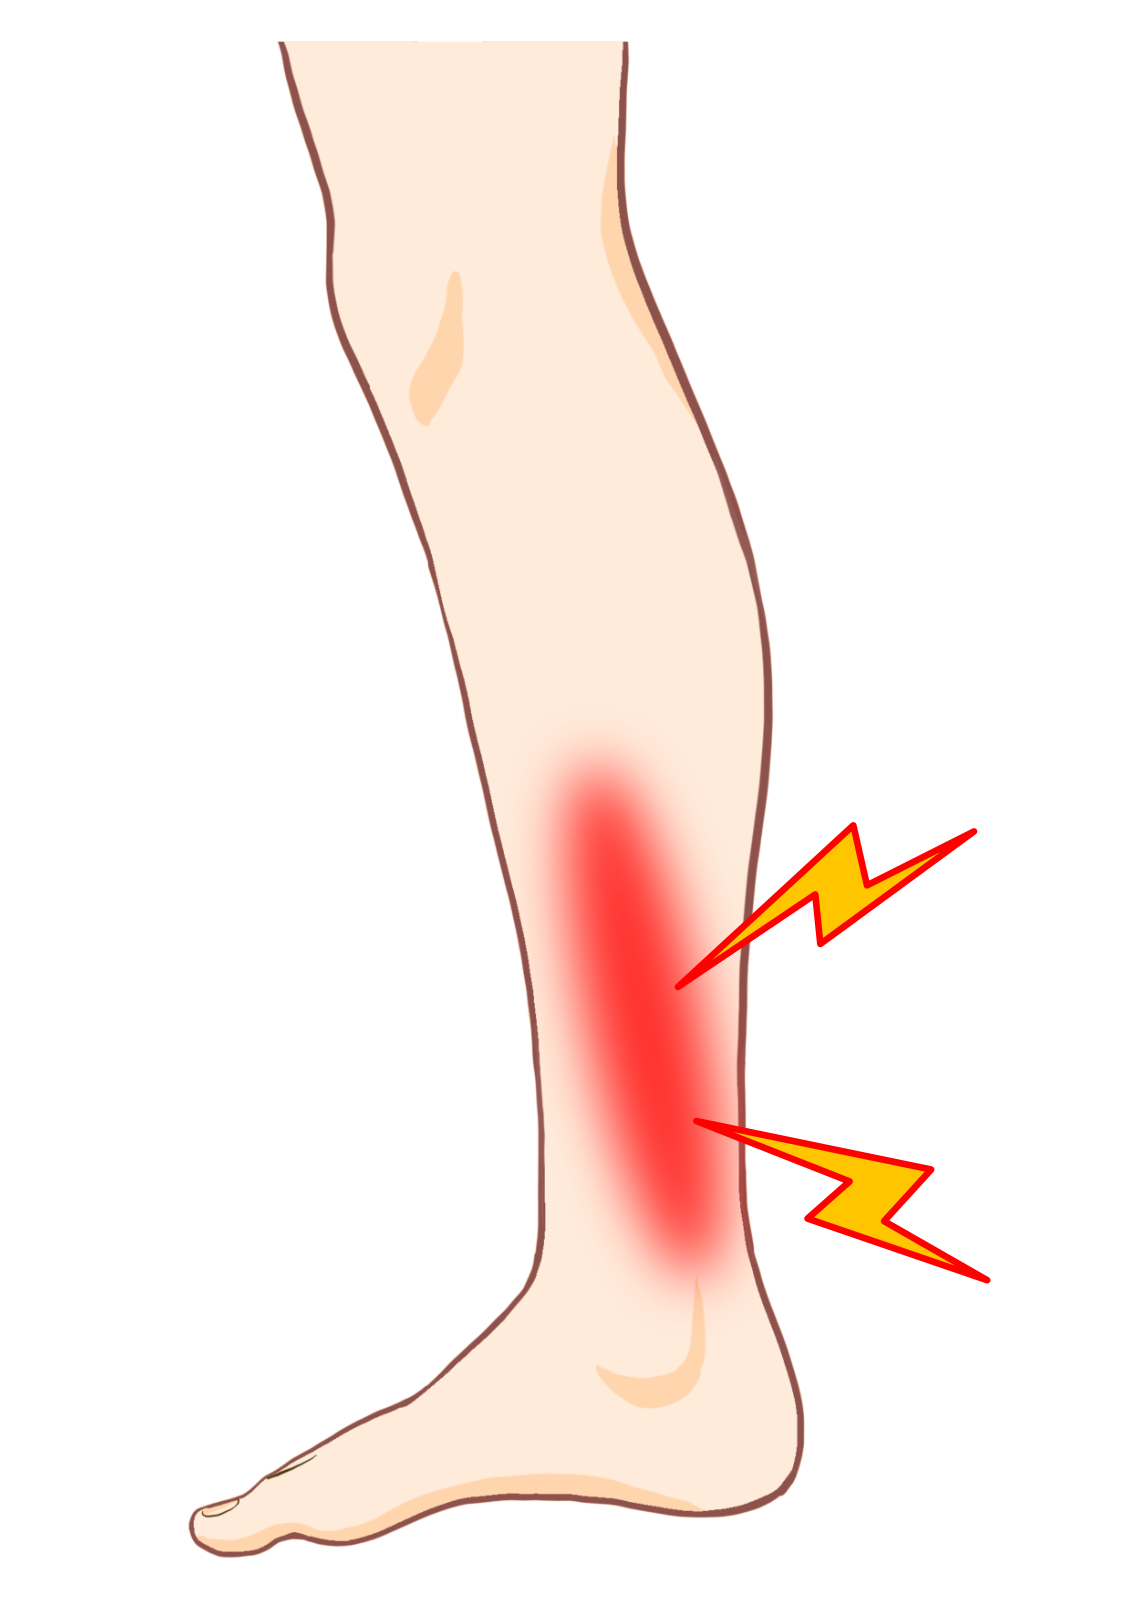

★シンスプリントの症状

初期の段階では運動時もしくは運動後に脛骨内側の中央から下方3分の1にかけてズキズキとした痛みや圧痛が生じます。

症状が進行すると安静時にも痛むようになり、次第に歩行困難になります。